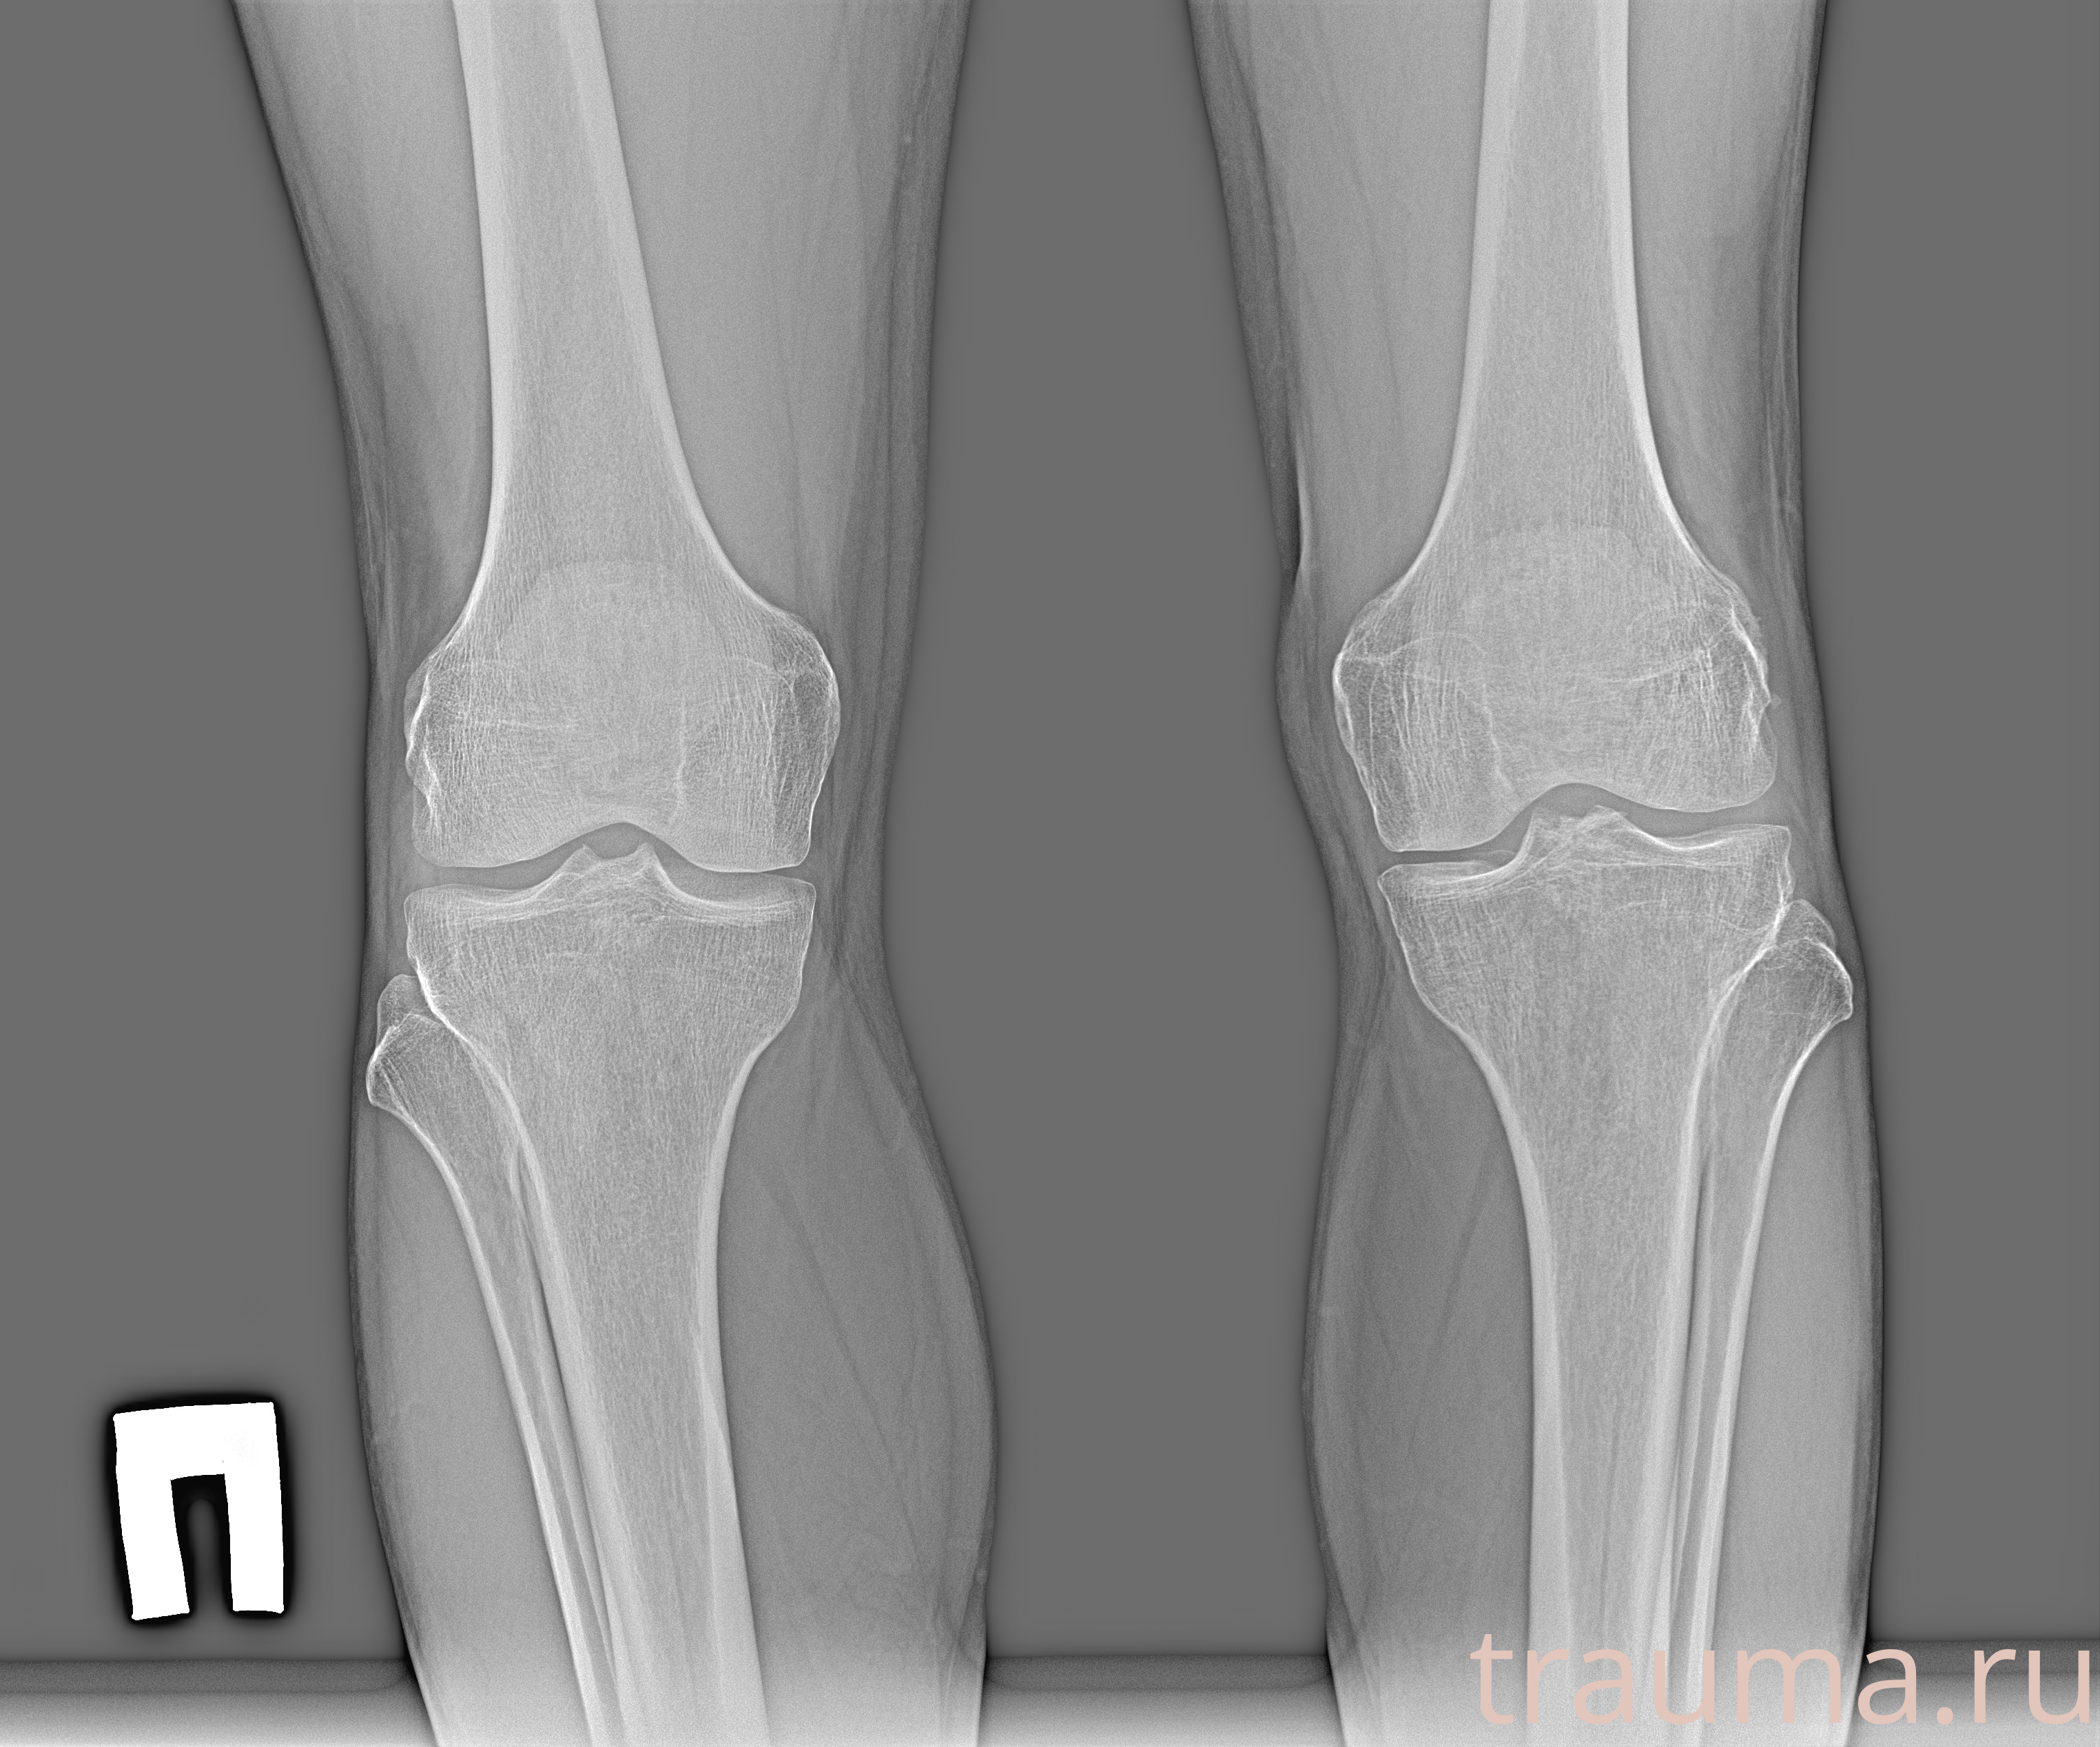

Рентген на дому: по вашему адресу приезжает врач-рентгенолог, травматолог-ортопед с мобильным рентгеновским аппаратом, проводит диагностику травмы или заболевания, делает необходимые рентгенограммы, дает рекомендации по дальнейшему лечению. Получить качественные снимки в домашних условиях возможно благодаря уникальной методике, разработанной МосРентген Центром для института  Склифосовского